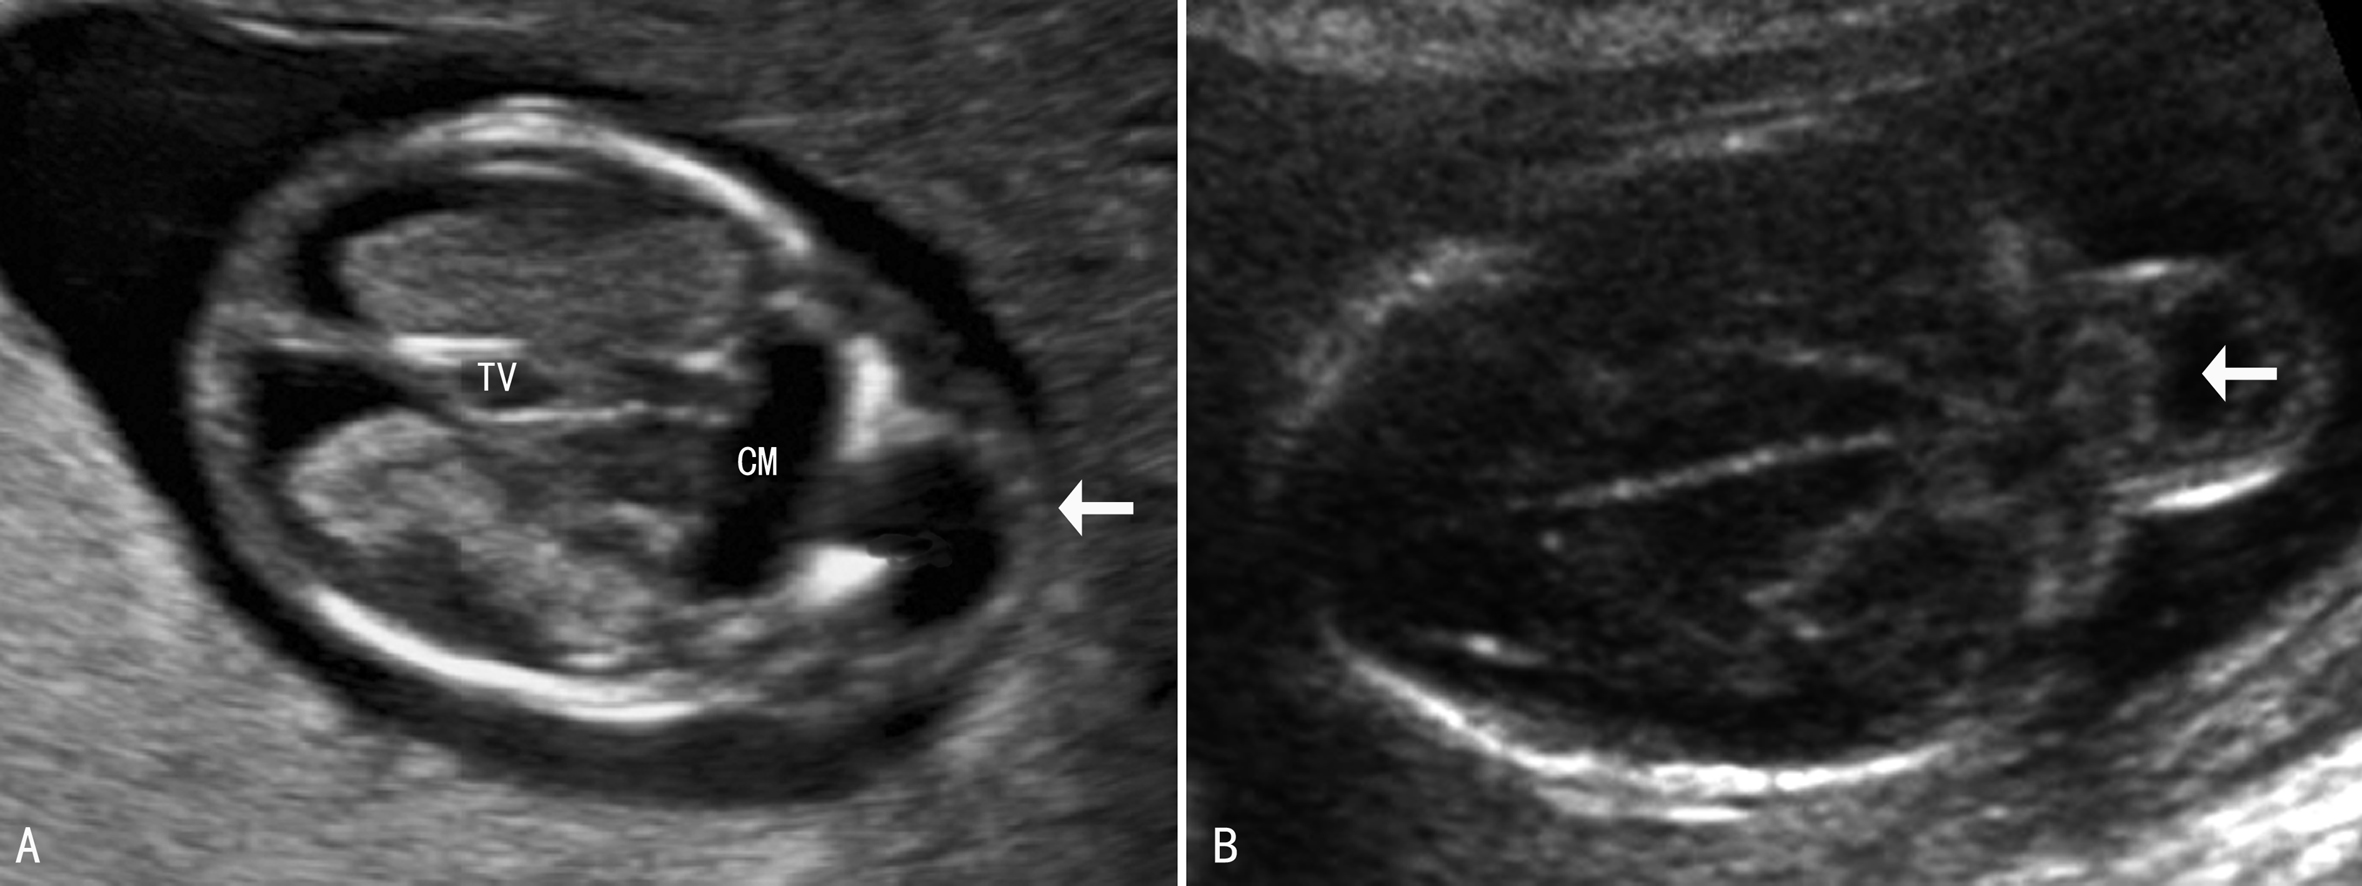

早孕期头颅小或者颅骨形态不规则,在头部轮廓外可显示包块样回声;随着胎儿的生长图像显示的愈加典型。经阴道超声可以看到早孕晚期的颅骨缺损处。胎儿颅骨显示后可以在颅骨外显示包块回声,局部颅骨显示缺损(图1),通过相互垂直的两个断面测量颅骨缺损的大小可以评估缺损的面积及突出物的大小(图2,图3)。有些小的缺损不能显示,仅能看到颅骨旁突出去的小囊样结构。突出的回声内部由于疝出的组织不同而有不同的表现,呈囊性或者囊实性混合回声(图1),“囊套囊”或者“靶环征”提示第四脑室脱垂,突出至颅底及眼部的脑膜膨出常难以于产前做出诊断。70%~80%伴有脑室扩张(图1A),25%伴小头畸形。除脑部异常回声外,其他部位检查可以发现伴发的畸形。

图1 14周胎儿脑-脑膜膨出声像图(箭头)